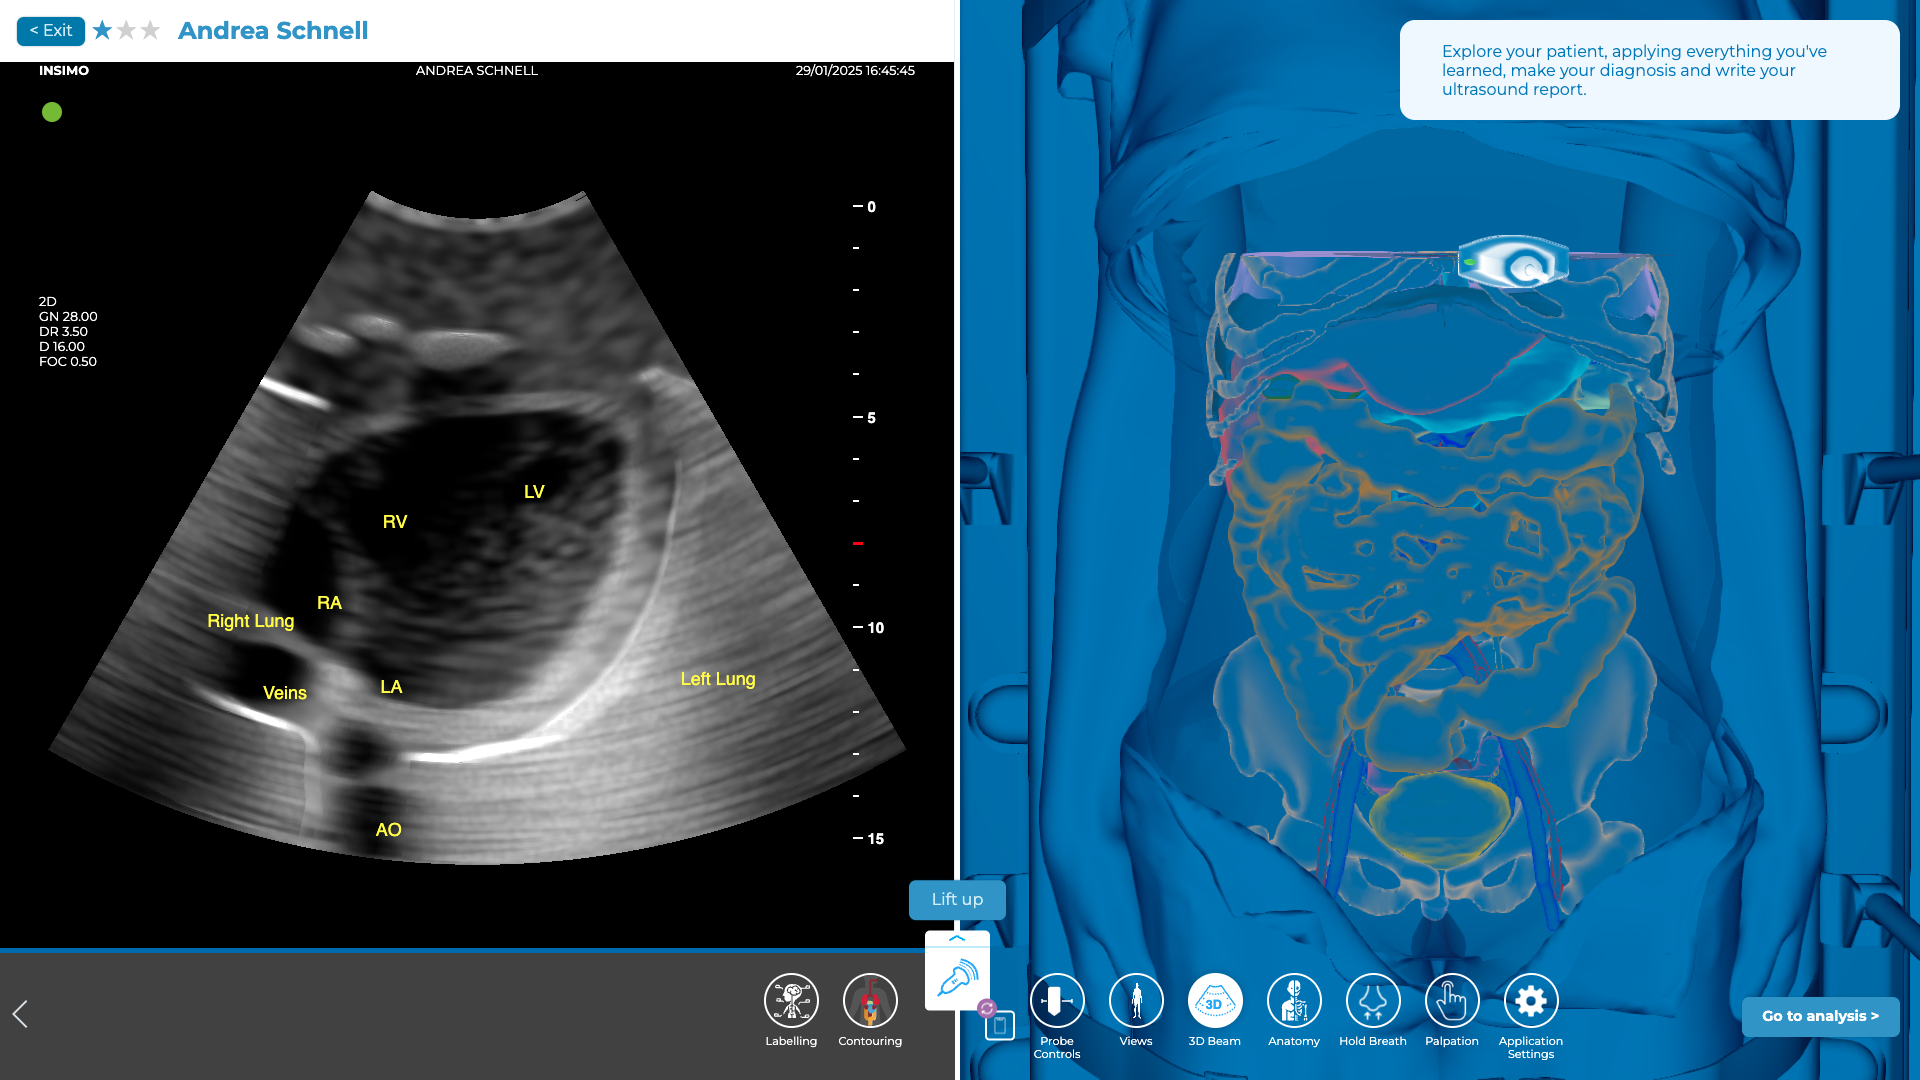

Evaluation de la vue péricardique (fenêtre sous-xiphoïde)

L’examen de la zone autour du cœur est crucial pour détecter la présence d’un épanchement péricardique, qui pourrait entraîner une tamponnade cardiaque, une urgence vitale nécessitant une prise en charge rapide. La tamponnade cardiaque se produit lorsque du liquide s’accumule dans le péricarde, comprimant le cœur et empêchant son bon fonctionnement, pouvant alors entraîner un arrêt circulatoire si non traité rapidement [6].

Pour visualiser cette zone, commencez par localiser le processus xiphoïde, situé à la base du sternum, juste sous la cage thoracique. Utilisez ce repère pour positionner la sonde juste à côté du processus xiphoïde, sur la gauche du patient. Cette position permet d’obtenir une vue du cœur, en particulier de la zone péricardique, entre le cœur et le diaphragme.

Placez la sonde en direction de l’axe longitudinal du sternum, en orientant légèrement la sonde vers le bas et à gauche. L’image obtenue permettra de visualiser la cavité péricardique, un épanchement dans cette zone, même petit, peut être à l’origine d’une tamponnade.

Exploration de la région péricardique sur diSplay U/S